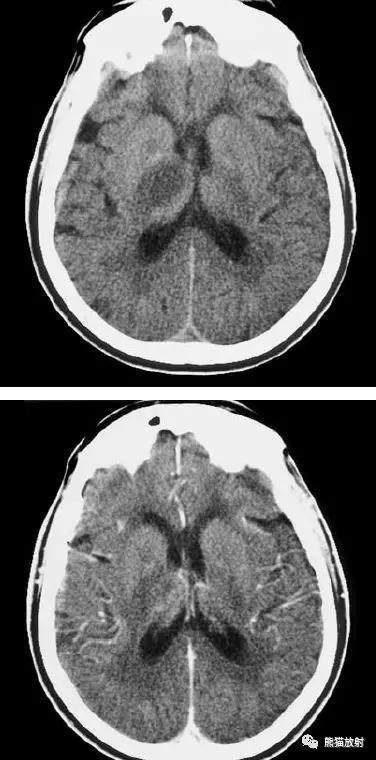

出血性脑梗死

上矢状窦血栓形成,呈高密度(箭头);并邻近脑实质内出血性脑梗死。